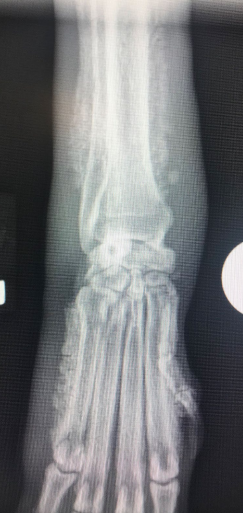

X-ray

- 사지에서 균일한 골막 증상(uniform periosteal proliferation).

- 처음에 Phalanges & metacarpal & metatarsal bones에서 관찰됨.

- 진행됨에 따라 골막 증식은 proximal(ulnar/radius, tibia/fibula)로 진행됨.

- Long bone의 관절 표면은 보통 정상적으로 보임.

- Firm soft tissue swelling of the distal extremities; 말단 사지에 단단한 연조직 부종 형성.

- 양쪽, 대칭적으로 골막 외부에 신생 조직 형성됨 - 초기에는 metatarsal/carpal bones의 축 아래쪽(abaxially)에서 관찰.

- 뼈의 축은 만성적인 경우 영향을 받음.